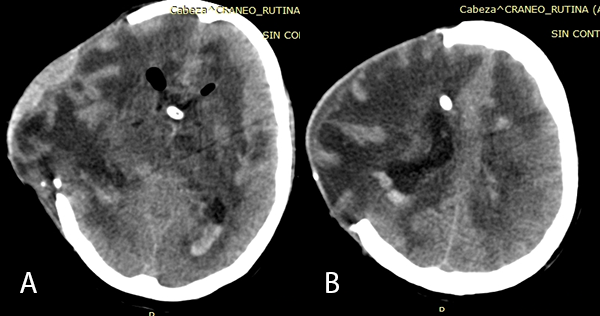

Imagen 5: (A) y (B) TEM cerebral sin contraste en cortes axiales post fenestración y colocación de nuevo DVE: se evidencia disminución de la asimetría ventricular y disminución de protrusión por defecto óseo craneal.

Se realizó la neuroendoscopía utilizando una óptica de 0 grados, de 30 cm. ingresando por el lóbulo frontal derecho. Inmediatamente al ingreso de la óptica se evidenciaron múltiples adherencias intra ventriculares. El foramen de Monro se encontraba parcialmente obstruido por una adherencia, además el epéndimo presentaba coloración amarillenta y las adherencias se encontraban difusamente en los ventrículos. Se intentó realizar una extracción de las membranas, pero se encontraban adheridas firmemente a las paredes ventriculares. (Imagen 4). Se realizó la fenestración del Septum Pellúcidum, con colocación de una nueva DVE, por lo que el paciente presentó mejoría clínica e imagenológica (Imagen 5).